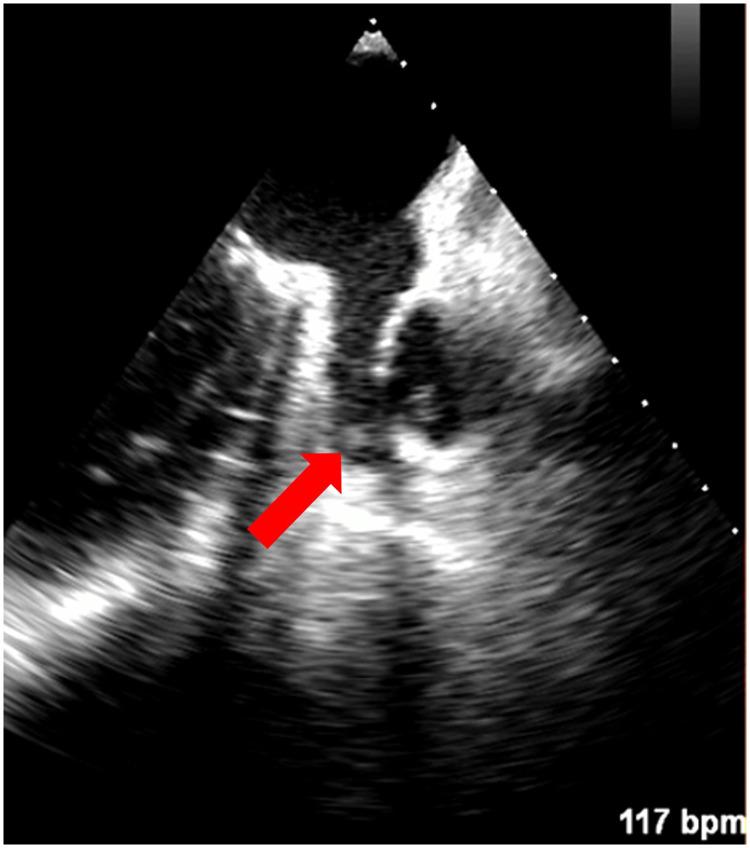

Left atrial appendage (LAA) thrombus is the most common source of embolization in atrial fibrillation (AF). Transesophageal echocardiography (TEE) is the gold standard method for LAA thrombus exclusion. Our pilot study aimed to compare the efficacy of a new non-contrast-enhanced cardiac magnetic resonance (CMR) sequence (BOOST) with TEE for the detection of LAA thrombus and to evaluate the usefulness of BOOST images for planning radiofrequency catheter ablation (RFCA) compared with left atrial (LA) contrast-enhanced computed tomography (CT). We also attempted to assess the patients' subjective experiences with TEE and CMR.

Seventy-one patients were enrolled. In 94.4%, both TEE and CMR excluded, and in 1 patient, both modalities reported the presence of LAA thrombus. In 1 patient, TEE was inconclusive, but CMR excluded LAA thrombus. In 2 patients, CMR could not exclude the presence of thrombus, but in 1 of those cases, TEE was also indecisive. During TEE, 67%, during CMR, only 1.9% of patients reported pain ( < 0.0001), and 89% would prefer CMR in case of a repeat examination. The quality of the left atrial contrast-enhanced CT scans was better compared with the image quality of the CMR BOOST sequence [8 (7-9) vs. 6 (5-7),  < 0.0001]. Still, the CMR images were useful for procedural planning in 91% of cases.

The new CMR BOOST sequence provides appropriate image quality for ablation planning. The sequence might be useful for excluding larger LAA thrombi; however, its accuracy in detecting smaller thrombi is limited. Most patients preferred CMR over TEE in this indication.

左心耳(LAA)血栓是心房颤动(AF)中最常见的栓塞来源。经食管超声心动图(TEE)是排除LAA血栓的金标准方法。我们的初步研究旨在比较一种新的非对比增强心脏磁共振(CMR)序列(BOOST)与TEE在检测LAA血栓方面的疗效,并评估与左心房(LA)对比增强计算机断层扫描(CT)相比,BOOST图像在规划射频导管消融(RFCA)中的实用性。我们还试图评估患者对TEE和CMR的主观体验。

共纳入71例患者。94.4%的患者TEE和CMR均排除LAA血栓,1例患者两种检查方式均报告存在LAA血栓。1例患者TEE结果不确定,但CMR排除了LAA血栓。2例患者CMR不能排除血栓存在,但其中1例TEE结果也不明确。在TEE检查期间,67%的患者报告疼痛,而在CMR检查期间,只有1.9%的患者报告疼痛(P<0.0001),89%的患者在重复检查时更倾向于CMR。与CMR BOOST序列的图像质量相比,LA对比增强CT扫描的质量更好[8(7-9)对6(5-7),P<0.0001]。尽管如此,CMR图像在91%的病例中对手术规划有用。

新的CMR BOOST序列为消融规划提供了合适的图像质量。该序列可能有助于排除较大的LAA血栓;然而,其检测较小血栓的准确性有限。在该适应症中,大多数患者更喜欢CMR而非TEE。